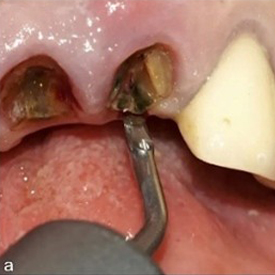

Figure 2: Syndesmotomy using the piezoelectric periotome (EX1 by W&H) (a), positioned in the periodontal ligament space at the level of the palatal fragments (b).